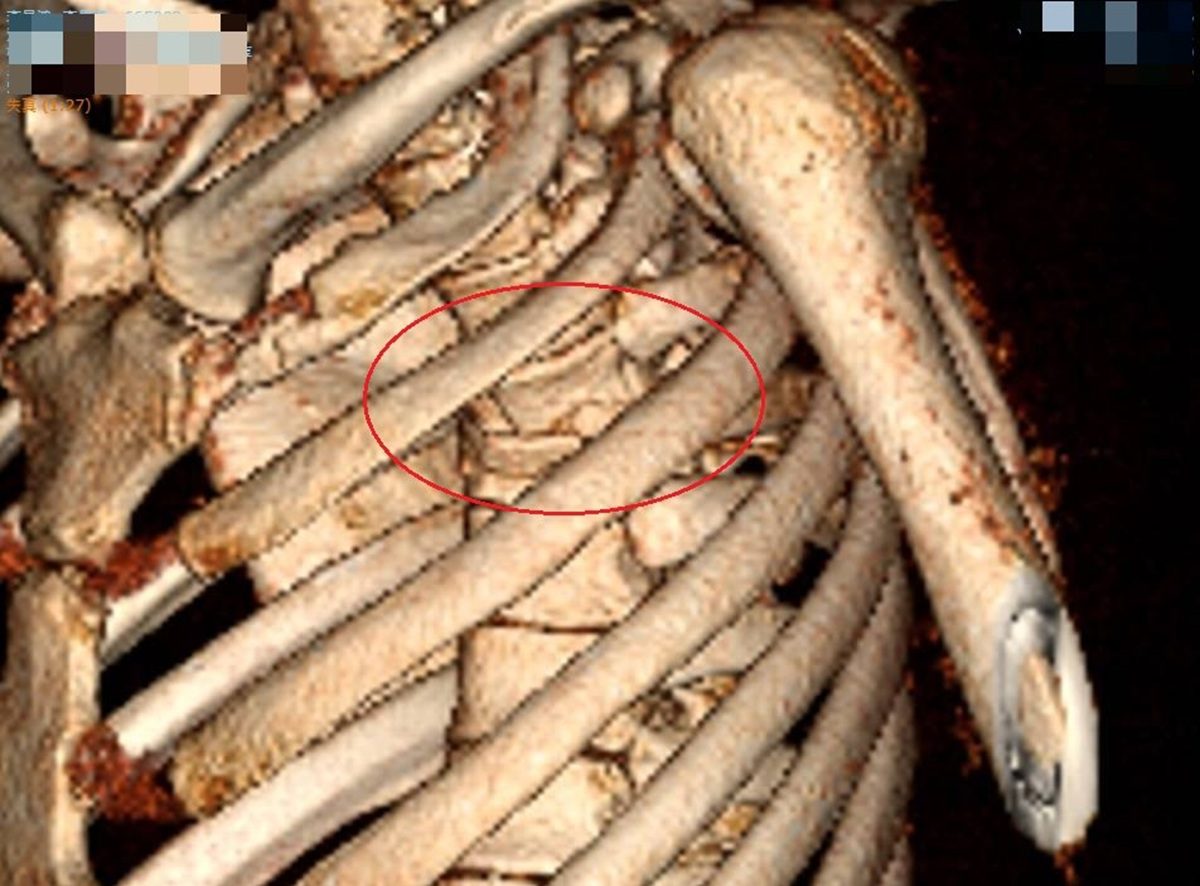

▲李先生胸部嚴重撞擊,屬於脊椎骨的胸椎第4節爆裂性骨折,壓迫到神經,雙腳無知覺,有癱瘓之虞。(圖/彰化醫院提供)

▲李先生胸部嚴重撞擊,屬於脊椎骨的胸椎第4節爆裂性骨折,壓迫到神經,雙腳無知覺,有癱瘓之虞。(圖/彰化醫院提供)

神經外科醫師張昕煥說,李先生胸部嚴重撞擊,屬於脊椎骨的胸椎第4節爆裂性骨折,壓迫到神經,雙腳無知覺,有癱瘓之虞,因此馬上手術,進行長達8小時的椎弓切除及神經減壓手術,並以10支鋼釘固定,手術順利,但李先生右腳還是不會動,肌力值0分,左腳稍微能動,肌力值2分,還是有下肢偏癱的可能。